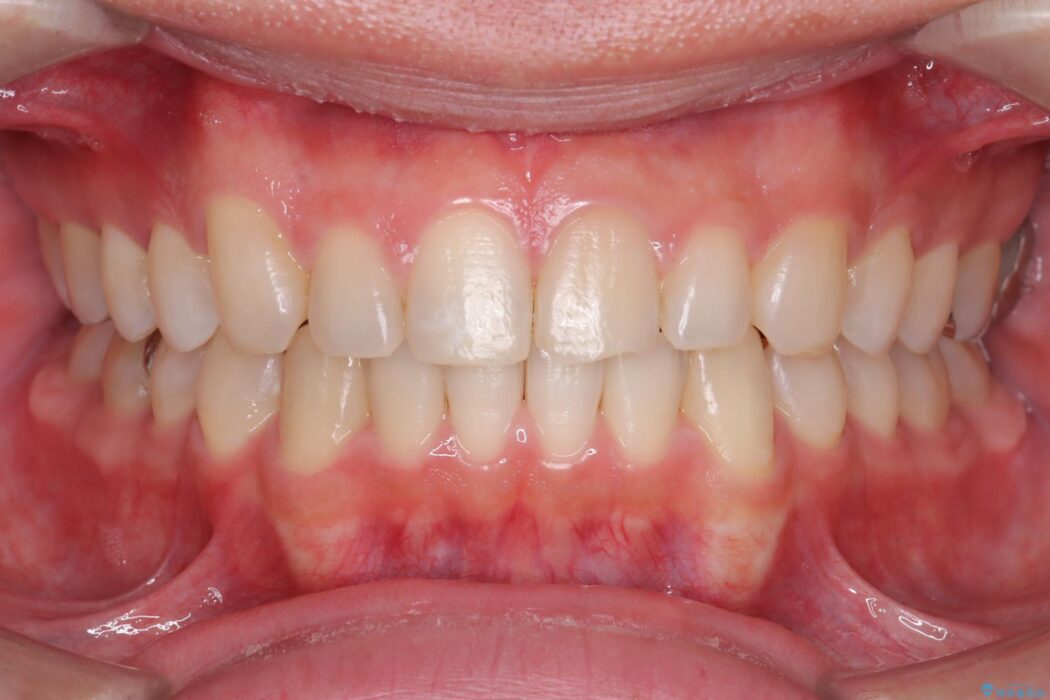

前歯の隙間とガタつきが気になるとご来院された患者様です。

歯の隙間とデコボコ、シザーズバイトも改善され、咬み合わせや見た目が整い、患者様にも大変ご満足いただけました。